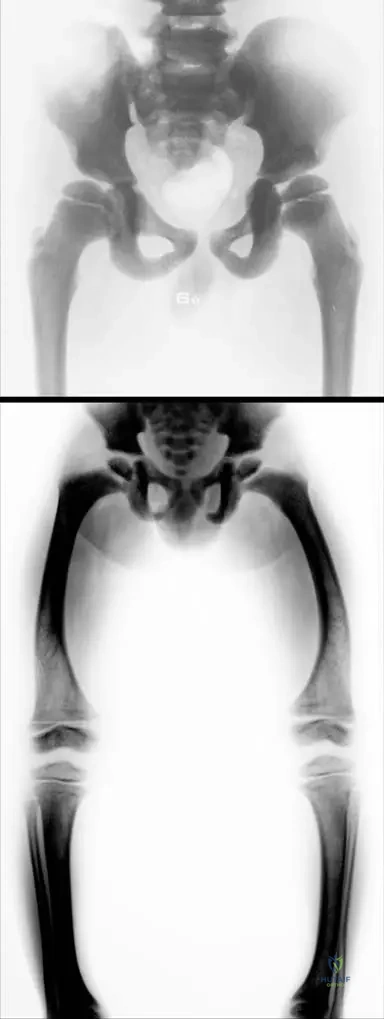

A 5-year-old boy with osteopetrosis has radiographs of his lower extremities, revealing diffuse increased bone density.

Rationale: The image description (Fig. 1.110) and the text state that in osteopetrosis, the "narrow medullar cavity" is observed. This narrowing is a direct consequence of the failure of osteoclasts to resorb bone, leading to the obliteration of the marrow space. The main distractor, widened, is incorrect as the medullary cavity is characteristically narrowed, not widened.

A 5-year-old boy presents with short stature, macrocephaly, and bilateral varus deformity of the knees. Radiographs reveal generalized osteosclerosis with narrow medullary cavities and widened metaphyses. Laboratory evaluation is likely to reveal which of the following?

A 5-year-old boy is evaluated for short stature and skeletal deformities. Radiographs of the pelvis and lower extremities demonstrate diffuse sclerosis, narrow medullary cavities, and widened metaphyses. These findings are characteristic of which condition?

Rationale: The description of sclerotic bony structure, narrow medullary cavity, and widened metaphyses in a young boy's radiographs is pathognomonic for osteopetrosis, particularly the early-onset form. Osteogenesis Imperfecta (A) is characterized by fragile bones and osteopenia, not sclerosis. Rickets (B) involves defective mineralization, leading to widened growth plates and bone deformities, but not diffuse sclerosis. Fibrous Dysplasia (D) presents with lytic lesions and ground-glass appearance, not generalized sclerosis. Paget's Disease of Bone (E) typically affects older adults and involves disorganized bone remodeling with both lytic and sclerotic phases, but not the diffuse, early-onset pattern seen here.

Rationale: The text explicitly states, "Th e structure of the bone metaphyses is damaged." Figure 1.110 also notes "widened metaphyses in this early form." This damage and widening of the metaphyses contribute to the skeletal deformities seen in osteopetrosis, such as varus deformities. While other structures might be indirectly affected, the metaphyses are specifically highlighted as damaged. The diaphyseal cortex (A) is sclerotic but not described as damaged in structure in the same way. The epiphyseal plate (B) is related but the metaphysis is the specific area mentioned. Articular cartilage (C) and periosteum (E) are not directly implicated in the primary structural damage described.